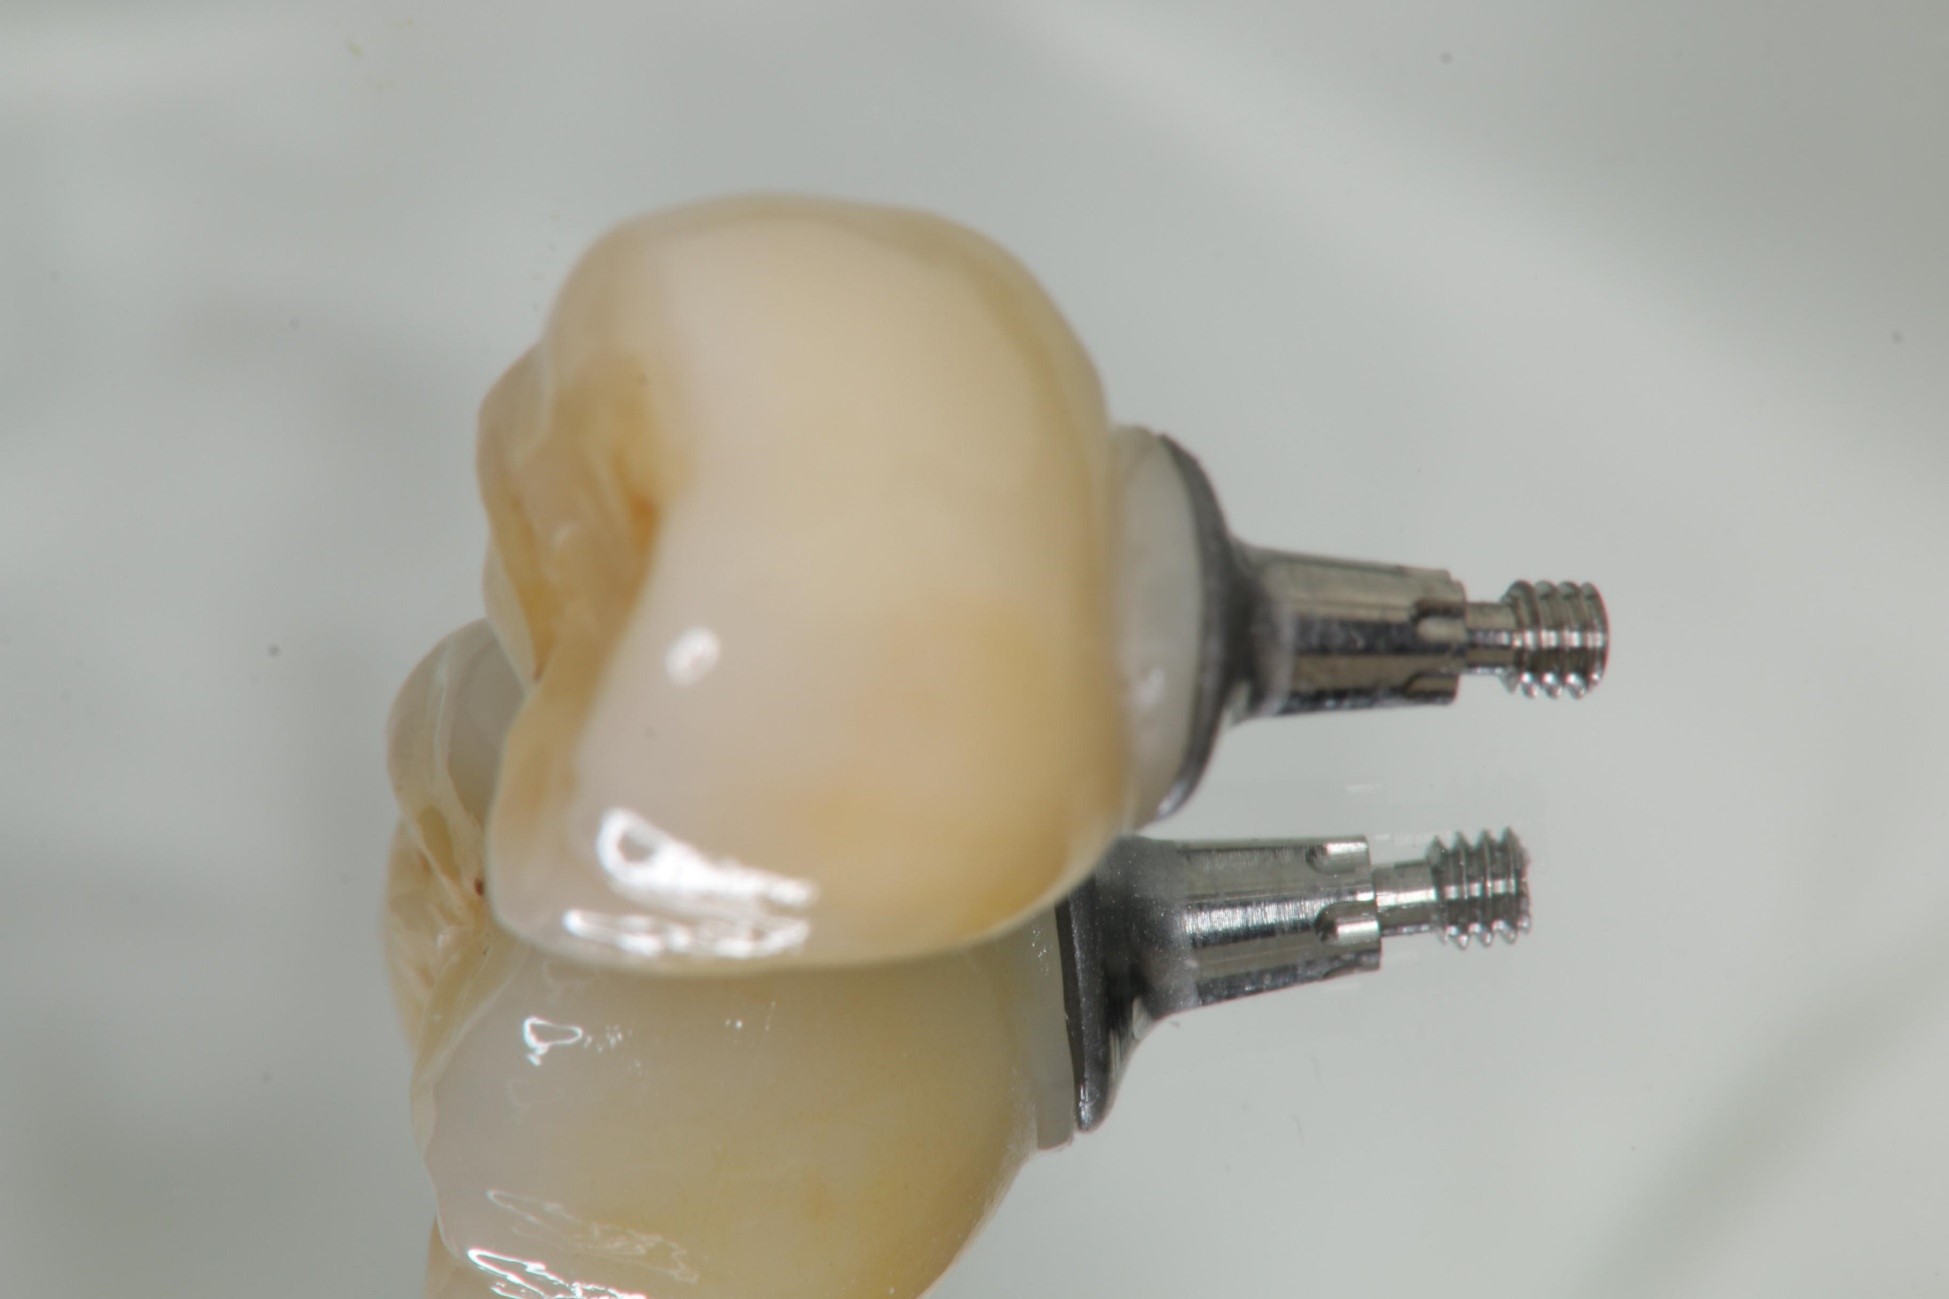

螺絲固定型假牙